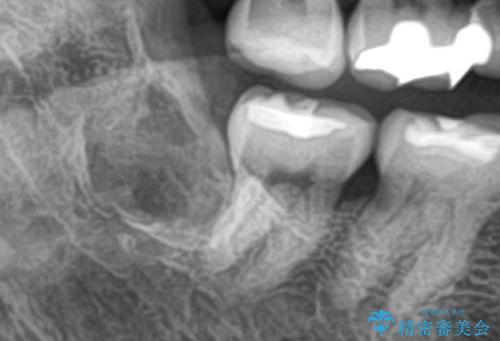

- 親知らずを抜歯したいとの事で来院。

パノラマ,CT撮影を行い安全なことを確認して抜歯を行いました。

抜歯後1週間後に抜糸と消毒を行い処置は完了になります。